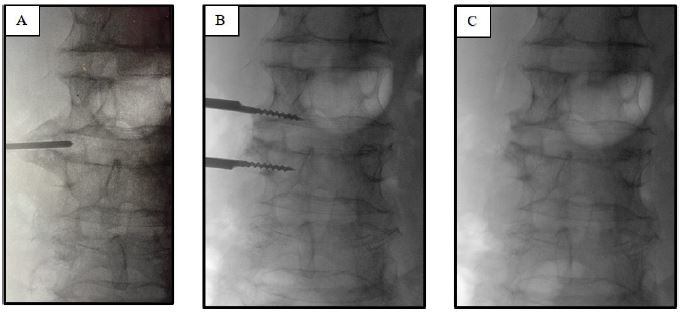

The bony spur was carefully drilled away, and an X-ray was performed to confirm the complete removal of the osteophyte (Figure 3B & C).

Figure 3: Lumbar X-ray imaging displaying lumbar tract before (A) and after the osteophyte’s drilling (B,C).